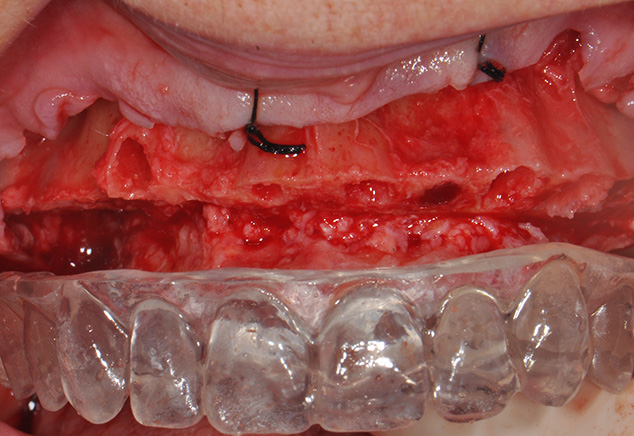

The patient was pre-medicated with oral sedation (Triazolam 0.25mg), amoxicillin, a steroid dose pack and chlorhexidine gluconate (CHG) rinse all starting 1 hour prior to surgery. The patient's chin and nose were marked with indelible marker, and the OVD was measured using a sterile tongue depressor with similar markings while the patient remained closed. The patient was then given full mouth local anesthesia. Starting with the maxillary arch, full thickness flaps were raised and sutured to the buccal mucosa with 4-0 silk to provide improved surgical access and vision. The teeth were removed with the goal of buccal plate preservation using the PIEZOSURGERY® (Mectron: Columbus, OH) for bone preservation (tips EX 1, Ex 2, Micro saw: OT7S-3). The sockets were degranulated with PIEZOSURGERY® (tip: OT4) and irrigated thoroughly with sterile water. With the anatomically correct surgical guide in position and firmly held in place by the surgical assistant, measurements were made from the mid-buccal of each tooth. Surgical cuts were made going from the anticipated cantilever of site #3 to site #14 using the PIEZOSURGERY® saw (tip: OT7 ). Our team goal was to create the prosthetic room necessary for a hybrid restoration i.e. 10-12 mm. The cuts were intentionally extended beyond the anticipated cantilever length to create adequate strength and thickness of the final prosthesis in these unsupported cantilever areas. (Fig 5, Fig 6) The mandibular arch was treated in a similar manner. Additionally, bilateral mandibular tori reduction were accomplished with the aid of the PIEZOSURGERY® saw (tip: OT7) after the extractions and prior to the vertical bone reduction of the mandibular ridge. Subsequently the implants were placed.